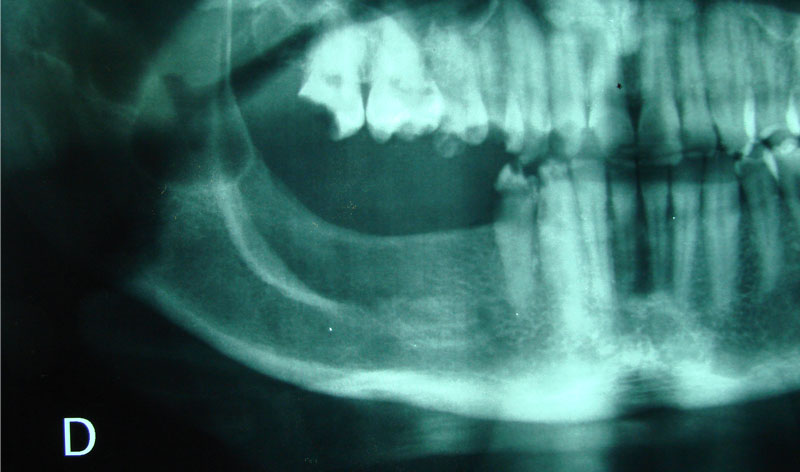

Son injertos del propio paciente extraídos del mentón o rama ascendente, destinados a aumentar la anchura del hueso indicados en maxilares con achura inferior a los dos milímetros.

Se deben fijar siempre con tornillos de 1.2 o 1.6 mm de osteosíntesis.

Terminada la reconstrucción ósea, es necesario esperar de 3 a 6 meses para la colocación de los implantes